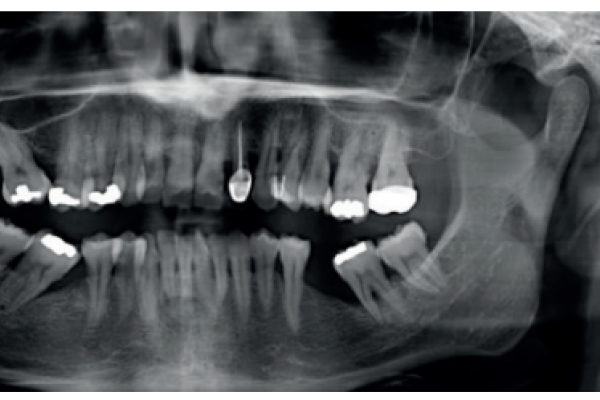

Atrofia combinada maxilomandibular. uso de implantes cortos y estrechos (BTI® CORE y BTI® 3.0)